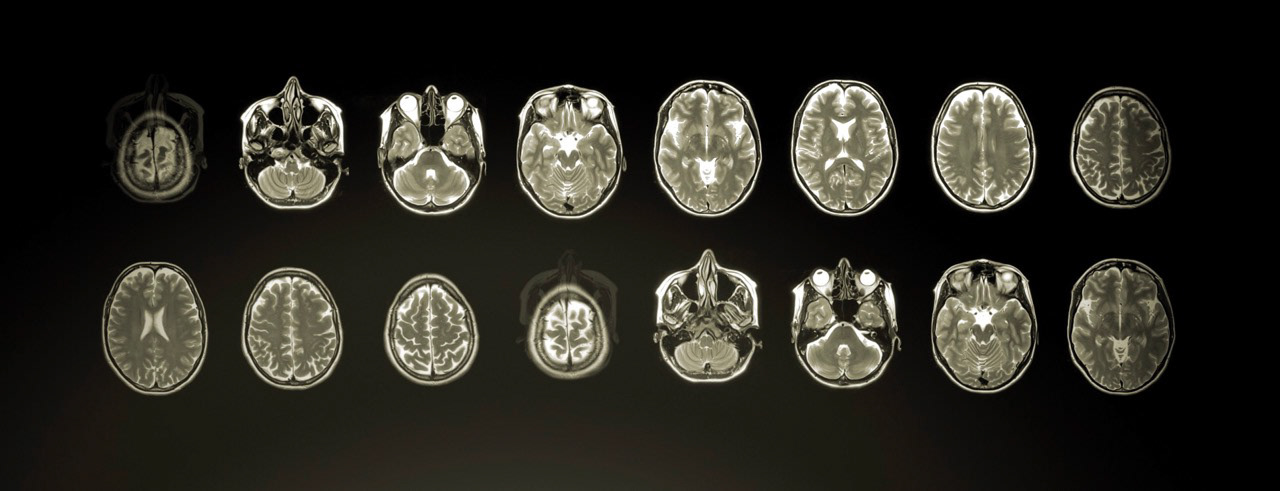

Grafisk produktionsdesign til Pernille Rose Grønkjærs dokumentarfilm Genetic Me. Filmen er en rejse ind i genernes verden i selskab med videnskabsjournalist og ph.d. i neurobiologi Lone Frank. Komplekse sammenhænge skulle beskrives filmisk